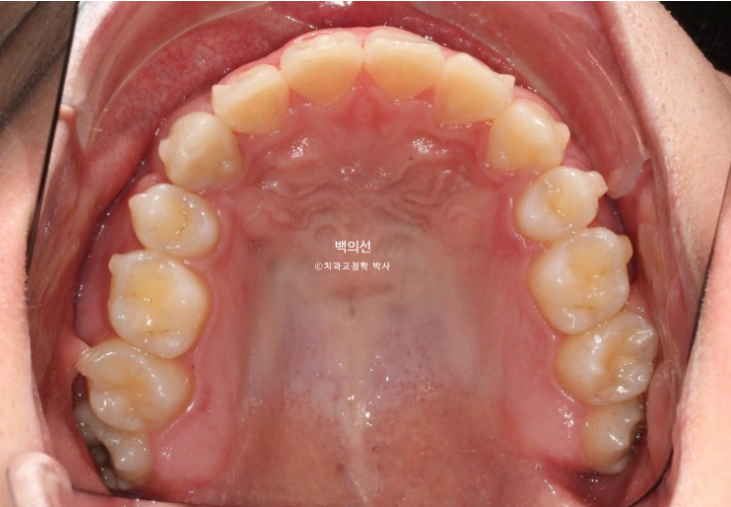

돌출입 수술을 하면 수술 테크닉적으로 작은어금니가 있던 공간이 약 2mm 이상이 남게 됩니다.

송곳니 뒤쪽에 2mm 의 공간이 각각 남았습니다.

이렇게 애매하게 남은 공간을 앞니 배열을 위한 공간으로 사용하는 것이 돌출입 수술교정의 핵심입니다.

이 정도의 남은 공간은 14개의 장치 안에서 해결 가능하기에 인비절라인 라이트로 충분합니다.